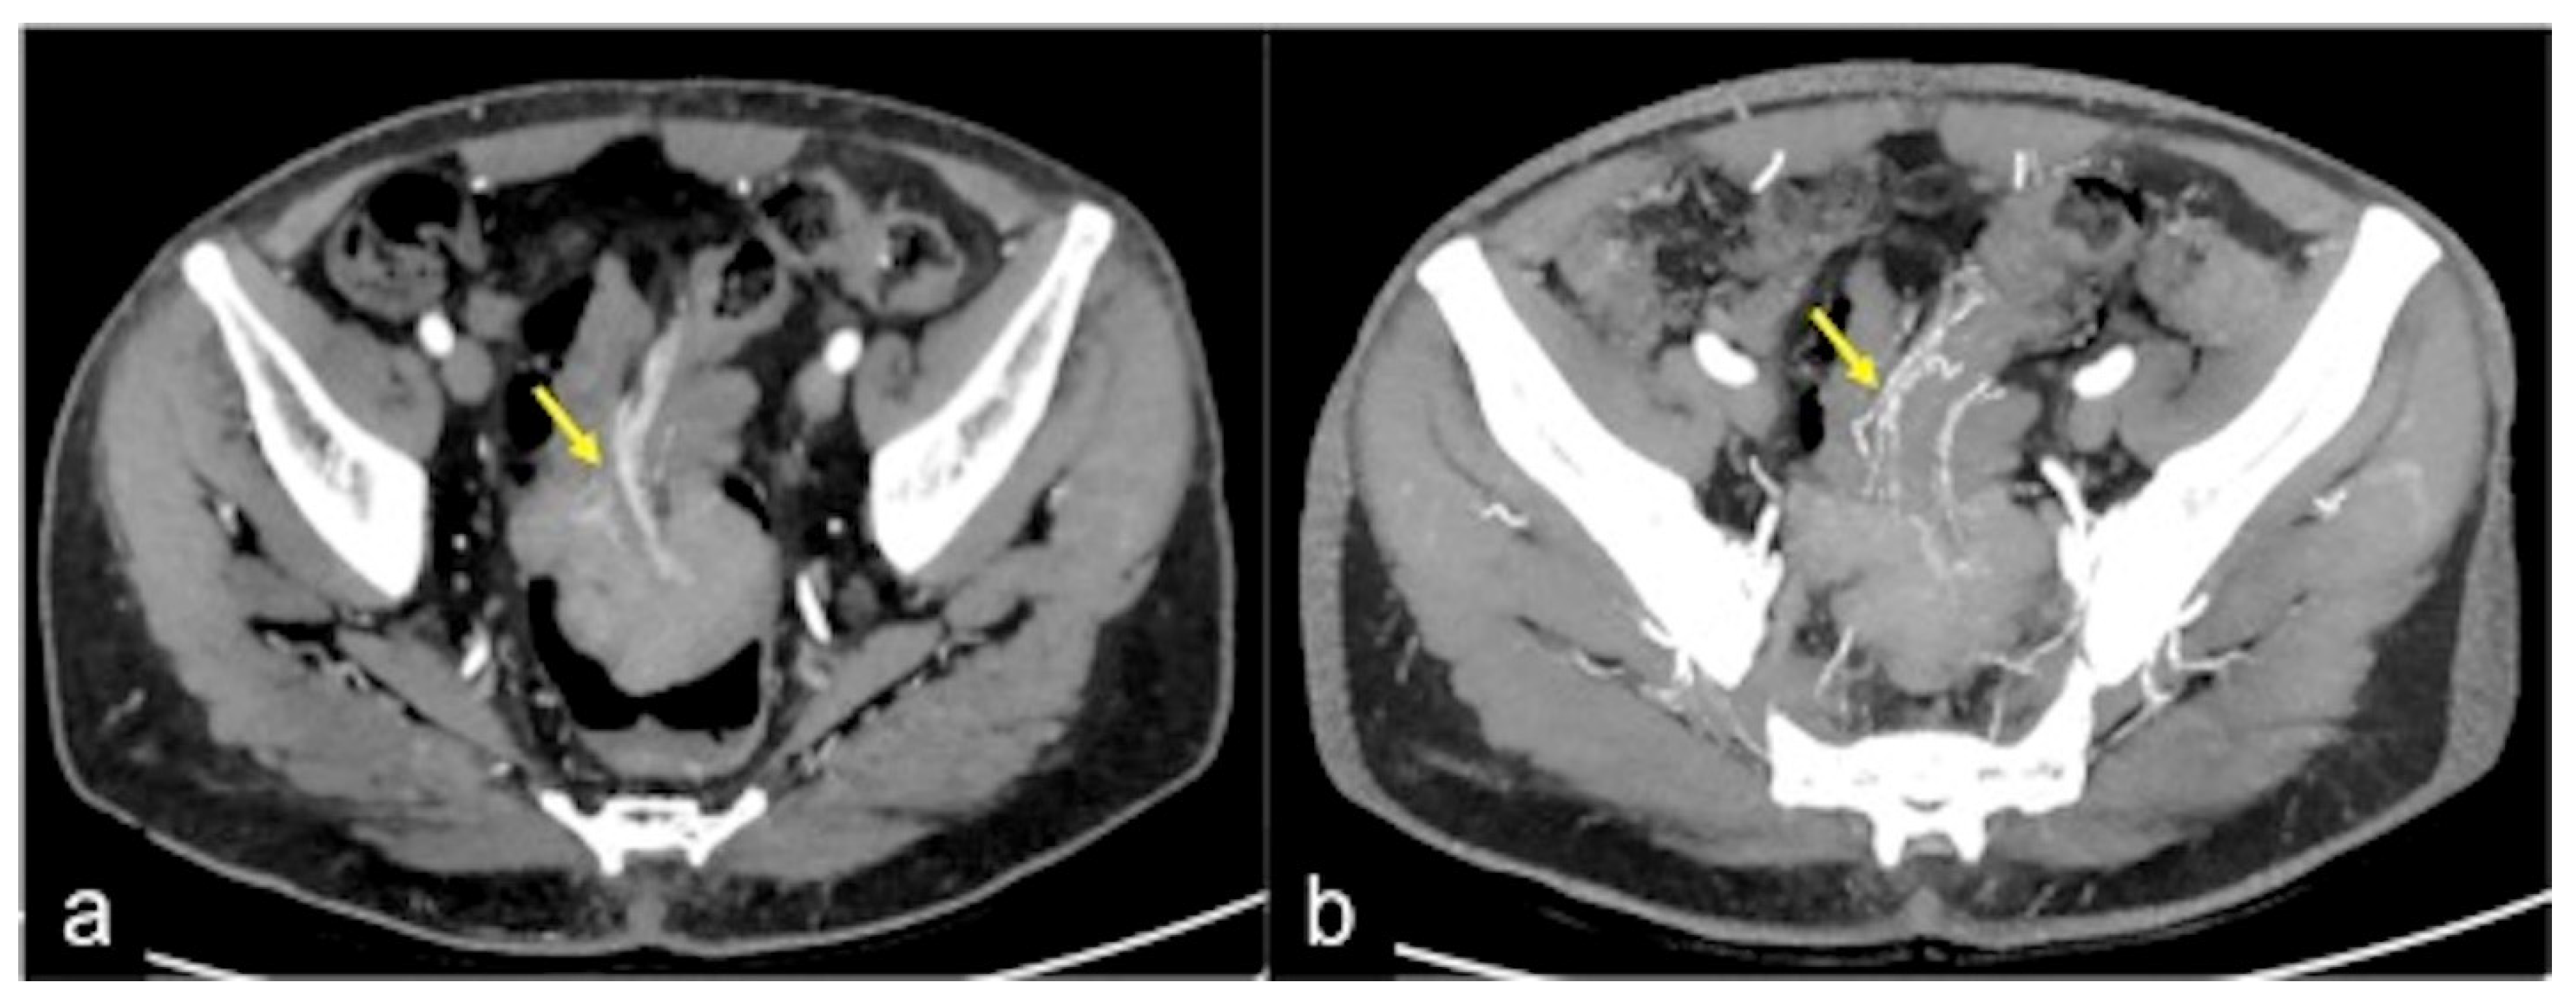

| Angiodysplasia (Figure 5 and Figure 34) | Asymptomatic or bleeding. | Small hyperdense nodules within the intestinal wall, best defined in the portal phase of the study. |

| Arterio-venous Malformation (Figure 17) | Haematochezia-rectorrhagia. | Vascular nidus with early opacification of the veins in the arterial phase. |

| Dieulafoy’s Lesion | Asymptomatic or bleeding. | Abnormally enlarged submucosal vessel, which may appear tortuous, linear or as a non-specific “blush” of contrast medium at the mucosal/submucosal level. |

| Rectal Varices and Haemorrhoids (Figure 35) | Pain and/or bleeding. | Dilated veins with possible bleeding visible in the portal phase; rectal varices are located proximal to the linea dentata while haemorrhoids are located in the anus. |